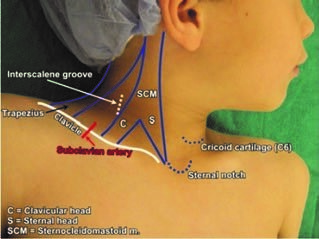

Position of the patient. The patient is placed in a supine position with the head turned contralateral to the side where the block needs to be performed (Fig. 1).

Figure 1. Position of the patient for performing the interscalene block

Anatomy and ultrasound characteristics. The three trunks emerging from the interscalene groove and pass downward and laterally to the subclavian artery. On this level, each trunk divides into anterior and posterior divisions. The linear probe needs to be placed coronal-oblique in the supraclavicular fossa (Fig. 3). The subclavian artery, the first rib and pleura should be visualized with the brachial plexus, which at this level appears as a hypoechogenic “cluster of grapes” posterolaterally to the subclavian artery (Fig. 4). In-plane technique is used, and the needle should be visible to avoid accidental puncture of vessels, nerves, and pleura. Always insert the needle from lateral to medial.

Figure. 3. Position of the linear probe in performing supraclavicular brachial plexus block